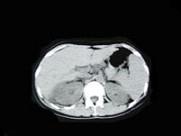

问题 女,33岁,右胁腹痛7天,尿检可见大量的脓细胞,CT平扫+增强如图所示,下列说法正确的是 ( )

选项 A.右肾体积增大,其内可见类圆形低密度病灶 B.增强扫描可见该病灶不均匀强化,其内有无强化的坏死灶 C.右肾病灶边界模糊不清 D.考虑为右肾囊肿合并感染 E.考虑为右肾脓肿

答案 ABCE